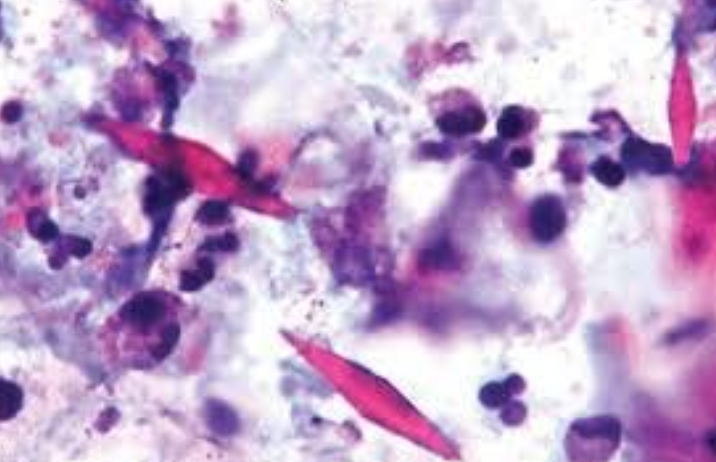

Cristales de Charcot-Leyden

Proteínas eosinófilicas galectina-10

¿Qué son los cuerpos de amianto?

Varillas de color marrón dorado, fusiformes con un centro translúcido